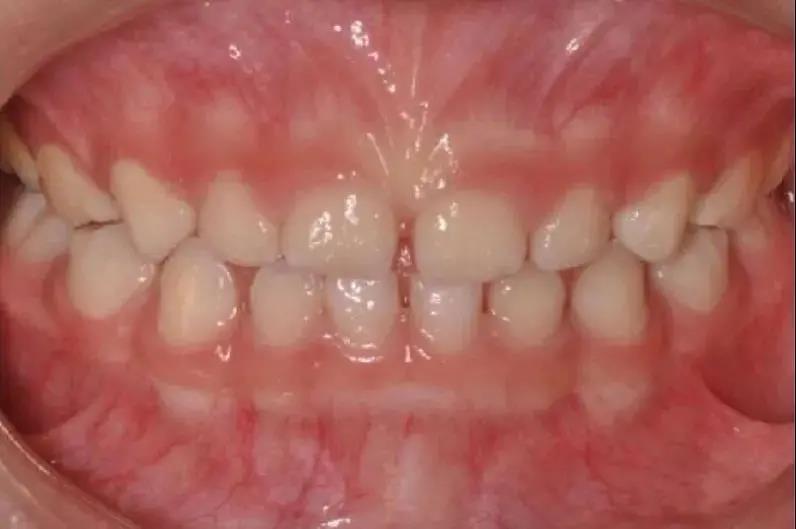

如發(fā)現(xiàn)孩子上下頜骨位置不佳

比如有明顯“齙牙”,應盡早矯治

錯合畸形不僅影響孩子的口腔健康

還會影響面容,

進而影響孩子的心理健康。

早期矯治可以充分利用兒童的頜骨發(fā)育潛能

調(diào)整頜骨的生長平衡及牙弓發(fā)育

因此齙牙還是要盡早診治哦